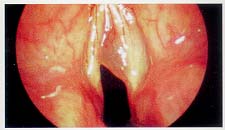

¼º´ëÀÇ º´¼Ò´Â Á÷Á¢ º´¼Ò¸¦

È®ÀÎÇÏ´Â °ÍÀÌ ÇʼöÀûÀÌ¸ç ¹æ¹ýÀ¸·Î´Â °£Á¢Èĵΰ˻ç¹ý, Á÷Á¢Èĵΰ˻ç¹ý, ÈÀ̹ö³»½Ã°æ µîÀ» ½ÃÇàÇÒ ¼ö ÀÖ°í ±×Áß, º»¿ø¿¡¼´Â °Ë»ç½Ã ȯÀÚ°¡ Å« ºÒÆíÀ»

´À³¢Áö ¾ÊÀ¸¸ç Á¤È®È÷ º´¼Ò¸¦ Áø´ÜÇÒ ¼ö ÀÖ°í ȯÀÚ ¹× º¸È£ÀÚµµ º´º¯À» ÇÔ²² °üÂûÇÒ ¼ö ÀÖ´Â ºñµð¿À ÈÀ̹ö³»½Ã°æ °Ë»ç¸¦ ½ÃÇàÇϰí ÀÖ´Ù.